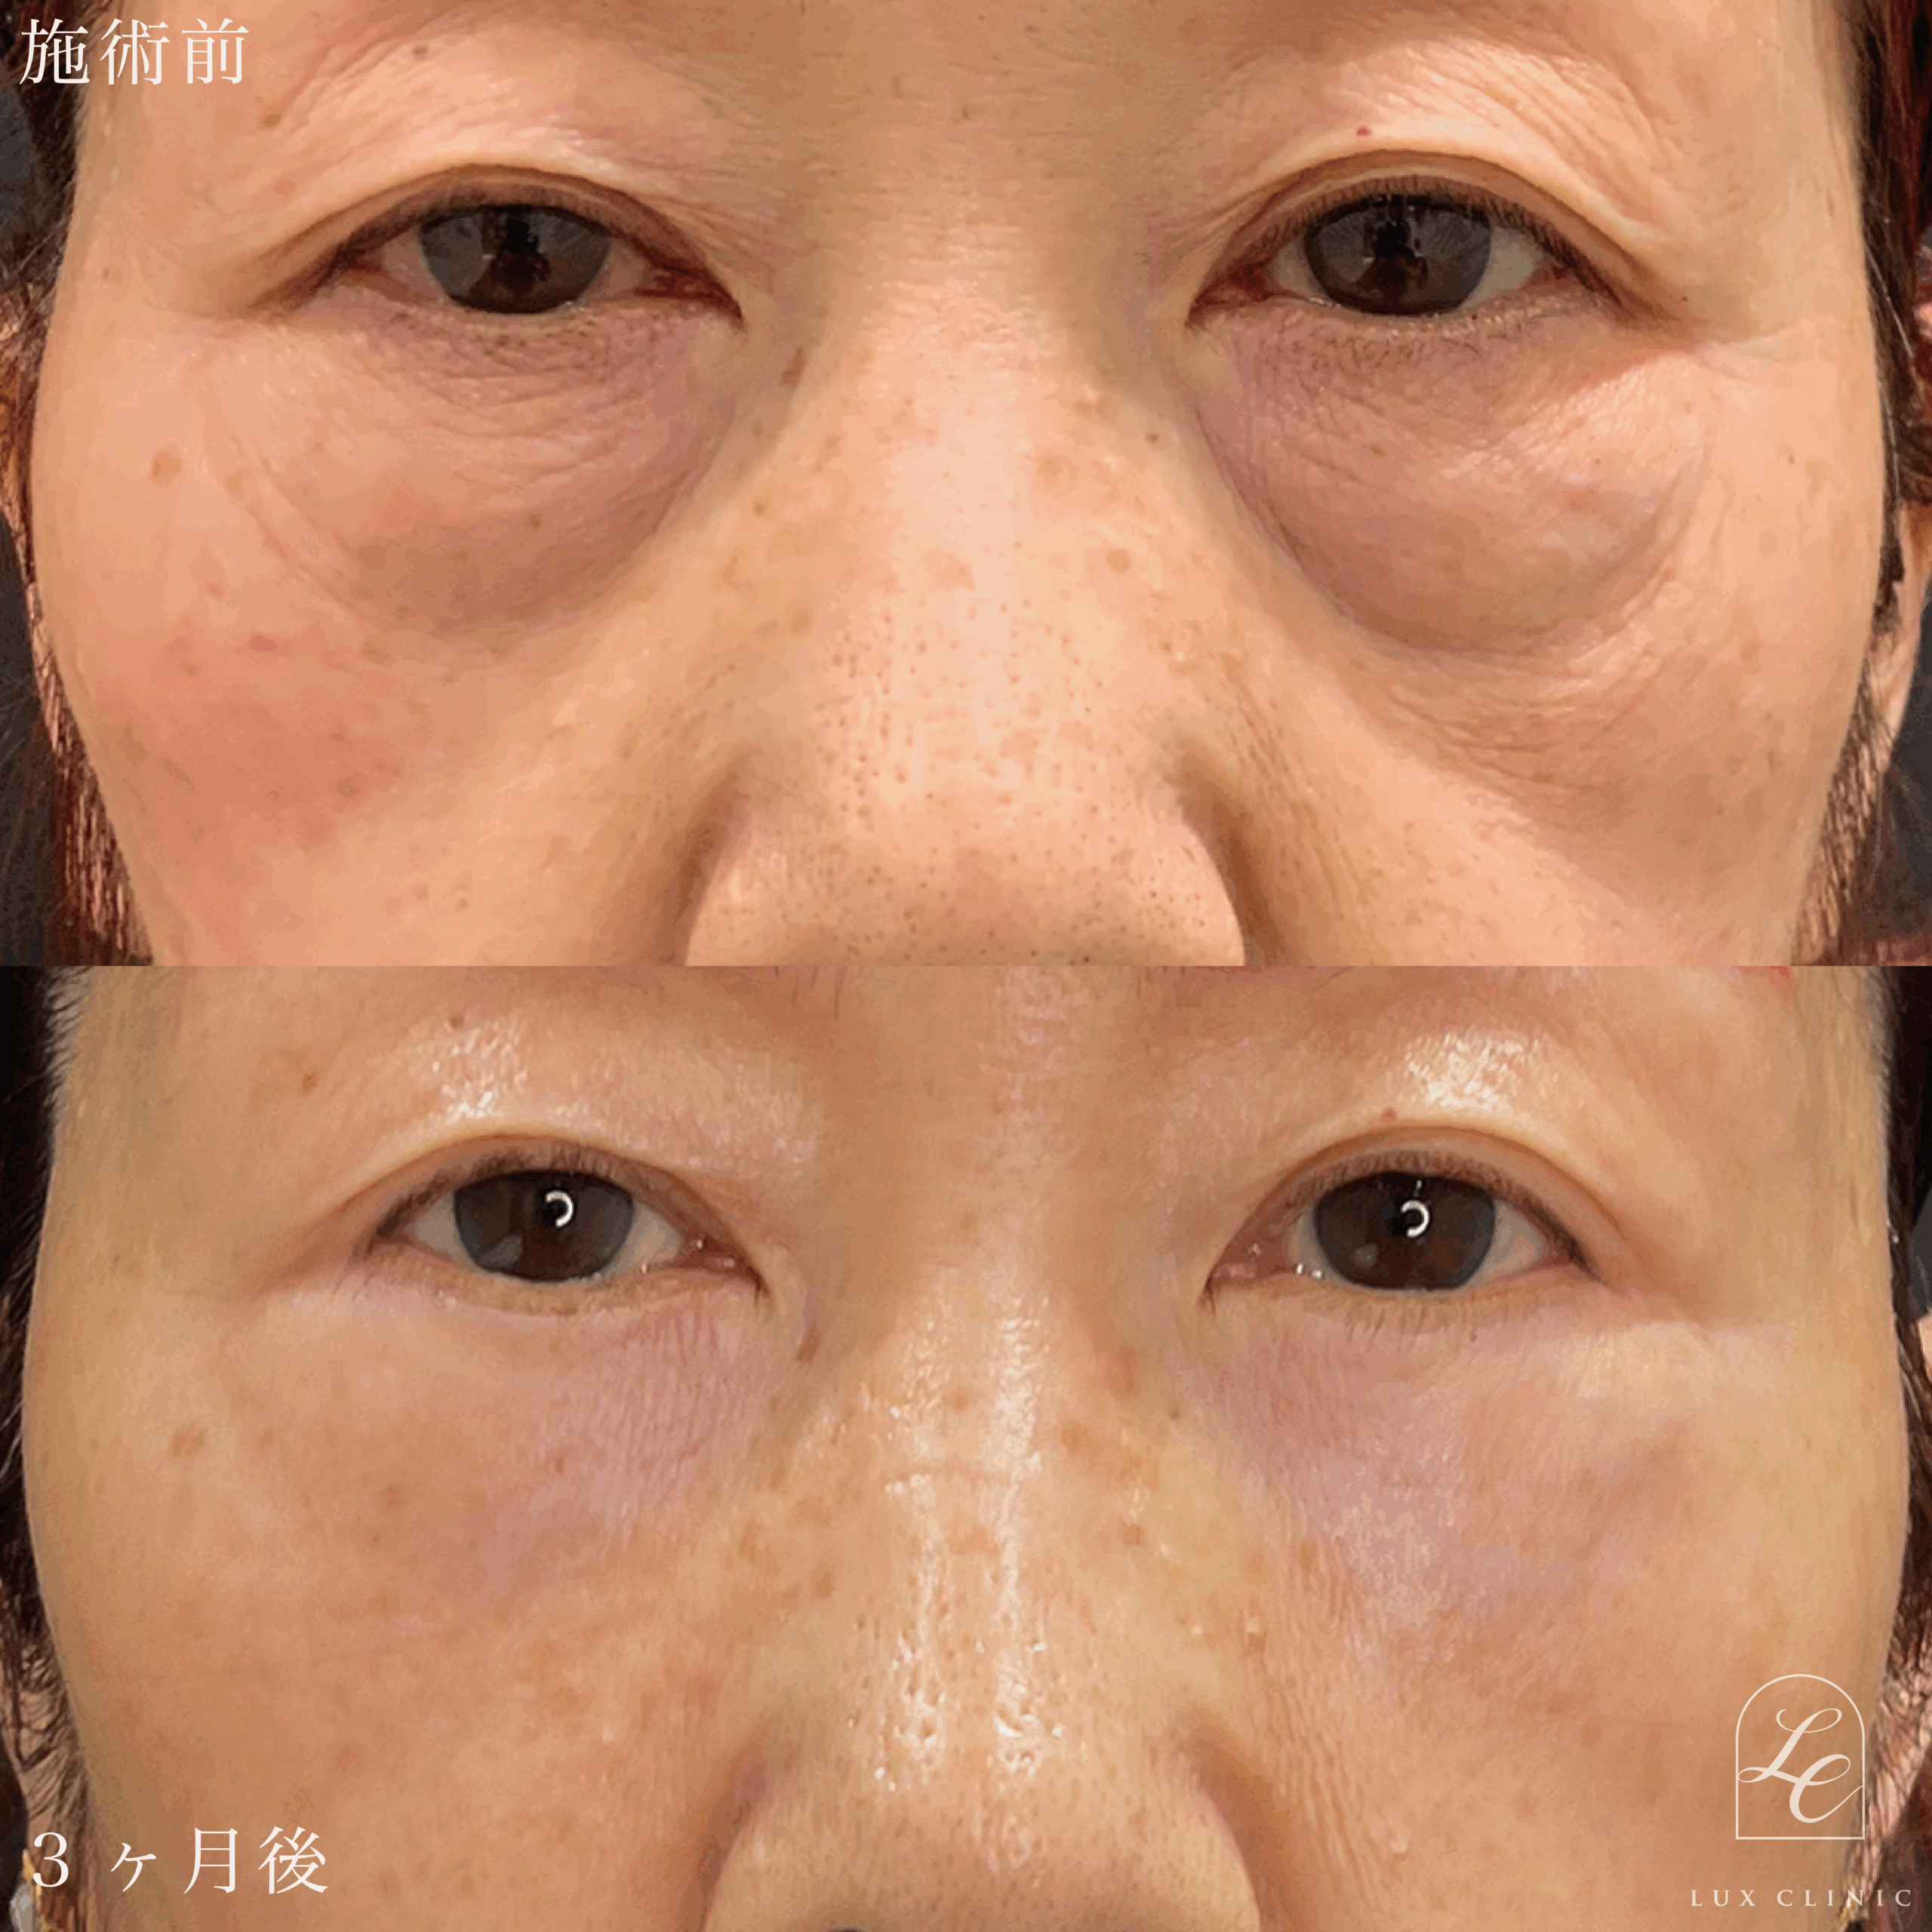

Case症例写真

表ハムラ法